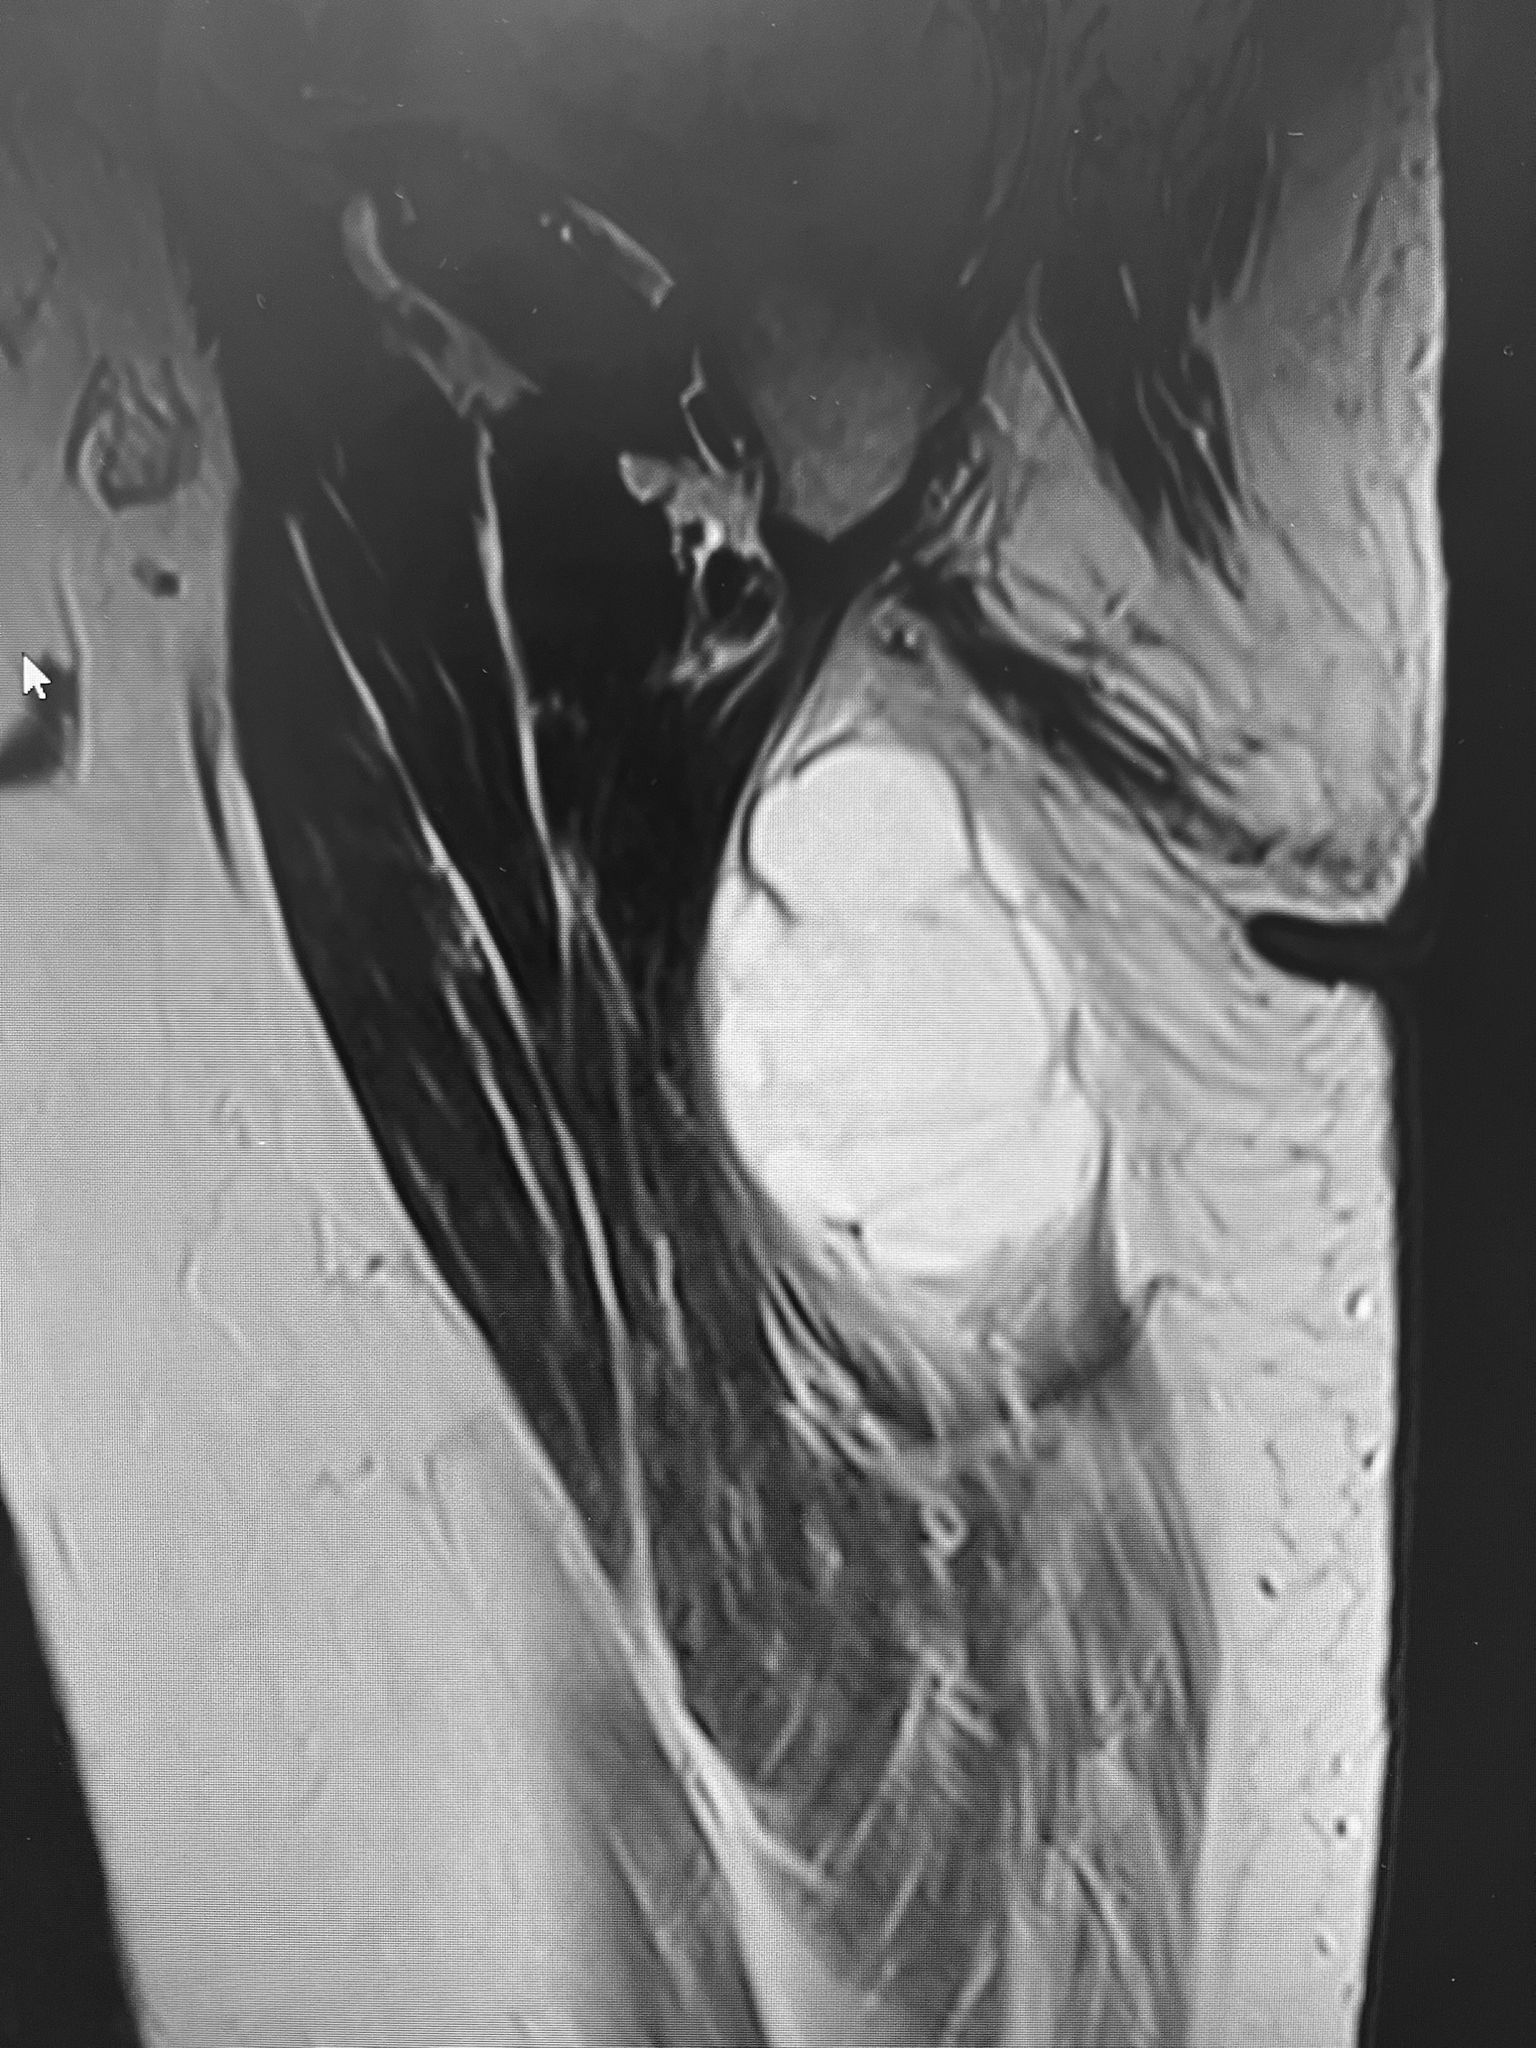

Tumoración de partes blandas en aspecto medial del tercio proximal de muslo izquierdo. Tumoración ovalada de contornos bien definidos, profunda, intramuscular entre las fibras mas posteriores y mediales del aductor mayor.

La tumoración muestra un aspecto multilobulado en T2, sin signos de sangrado ni componente adiposo.

No se aprecia restricción en difusión, todo ello compatible con mixoma.